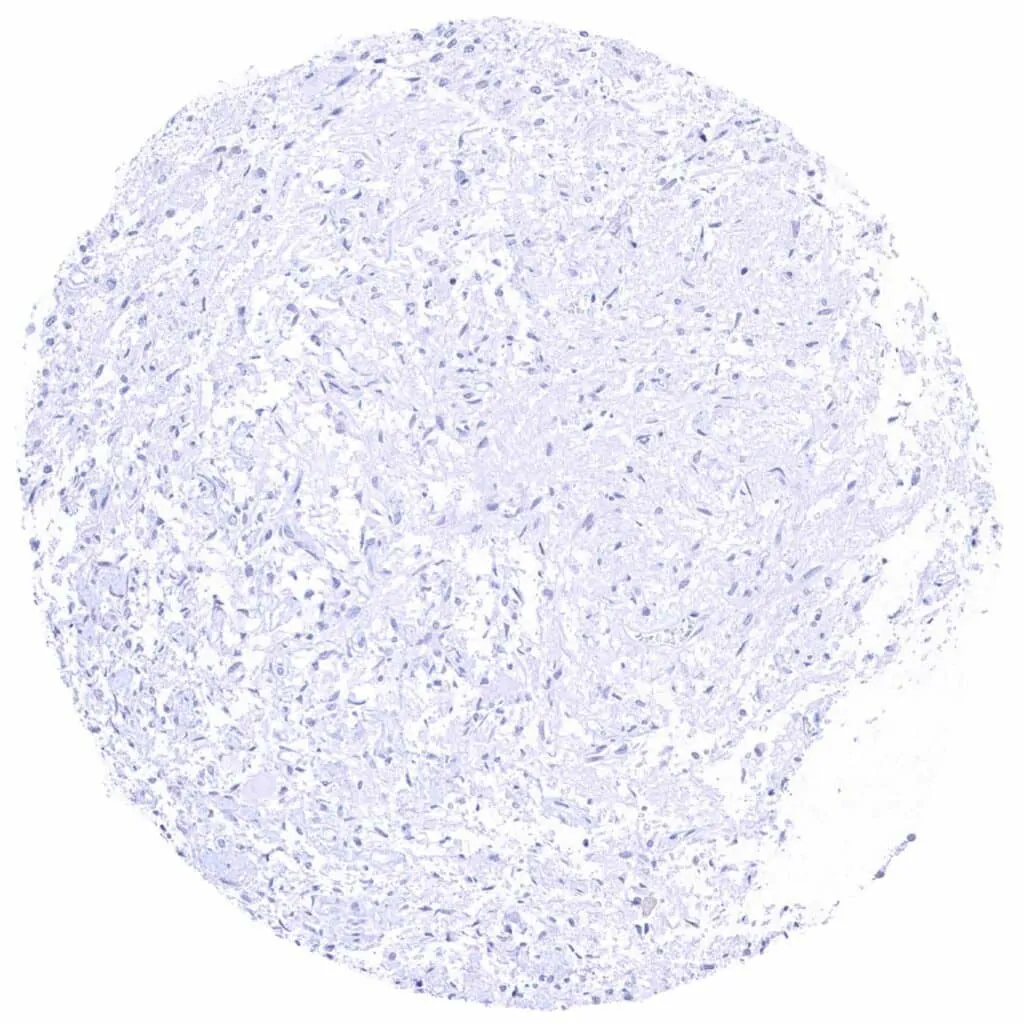

Aorta, media